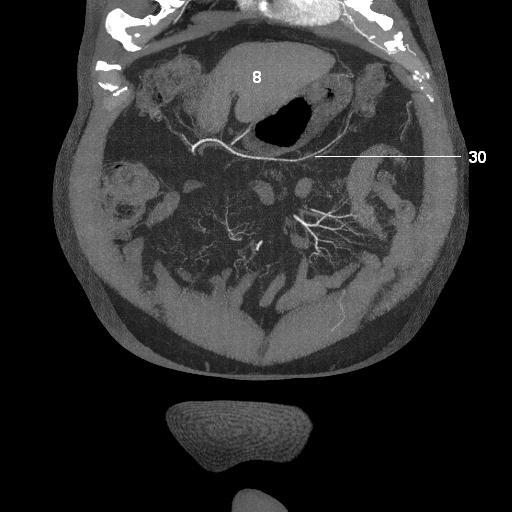

8.   liver

30. middle colic artery